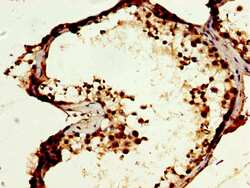

- Main image

- Experimental details

- Immunohistochemical analysis of MOS in paraffin embedded human testis tissue using a MOS polyclonal antibody (Product # PA5-97978) at a dilution of 1:400. After dewaxing and hydration, antigen retrieval was mediated by high pressure in a citrate buffer (pH 6.0). Section was blocked with 10% normal goat serum 30min at RT. Then primary antibody (1% BSA) was incubated at 4°C overnight. The primary is detected by a biotinylated secondary antibody and visualized using an HRP conjugated SP system.